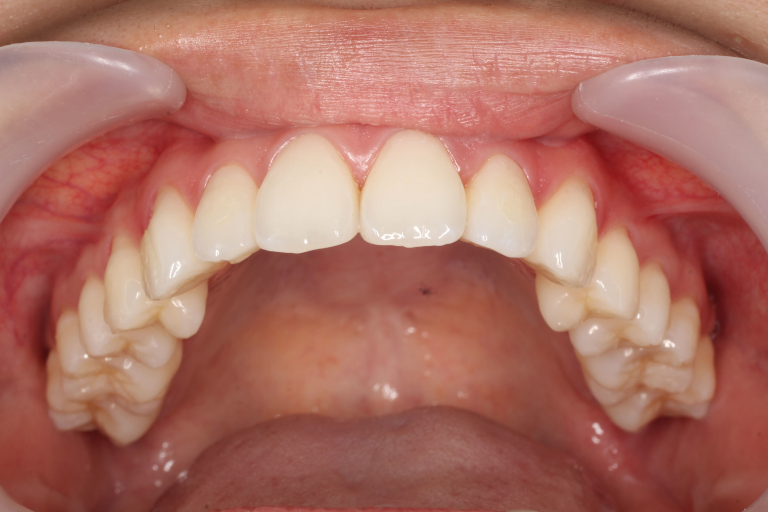

Before

After

| 主訴 | 歯並びの乱れ(叢生)があり、口元の突出感を抑えたい |

| 治療内容 | インビザラインを用いた治療 (非抜歯ケース) |

| 治療期間 | 1年7ヶ月 |

| 治療費用 | 基本料金:660,000円 調整料:3,300円 × 24回 |

| リスク | 取り外し式装置で、1日24時間中22時間使用しなければならず、しっかりと装置を装着できないと歯は思ったように動きません。 |